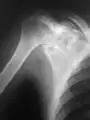

A variety of imaging studies can be used to diagnose chondroblastoma, with radiographs being the most common.[10][8] Laboratory studies are not considered useful.[14] Classical chondroblastoma (appearing on long bones) appears as a well-defined eccentric oval or round lytic lesion that usually involves the adjacent bone cortex without periosteal reaction.[10][13] A sclerotic margin can be seen in some cases.[10][13] For long bone chondroblastomas the tumor is typically contained to the epiphysis or apophysis but may extend through the epiphyseal plate.[10][13] Chondroblastomas are usually located in the medullary portion of bones and can, in some cases, include the metaphysis.[10][13] However, true metaphyseal chondroblastomas are rare and are typically the result of an extension from a neighboring epiphyseal legion.[10][13] Most lesions are less than 4 cm.[10] A mottled appearance on the radiograph is not atypical and indicates areas of calcification which is commonly associated with skeletally immature patients.[10] Additionally, one-third of all cases involve aneurysmal bone cysts which are thought to be the result of stress, trauma or hemorrhage.[10] In cases involving older patients or flat bones, typical radiographic presentation is not as common and may mimic aggressive processes.[10][13]

Other imaging techniques involve computed tomography (CT), magnetic resonance imaging (MRI), and bone scans, which may be helpful in determining the anatomical boundaries, associated edema, or biological activity of the chondroblastoma, respectively.[8][10] MRI studies may show extensive oedema around the lesion and show variable T2 signal intensity.[15]

1. a. X-ray of chondroblastoma of thigh bone near knee -

2. X-ray of chondroblastoma of shoulder blade -